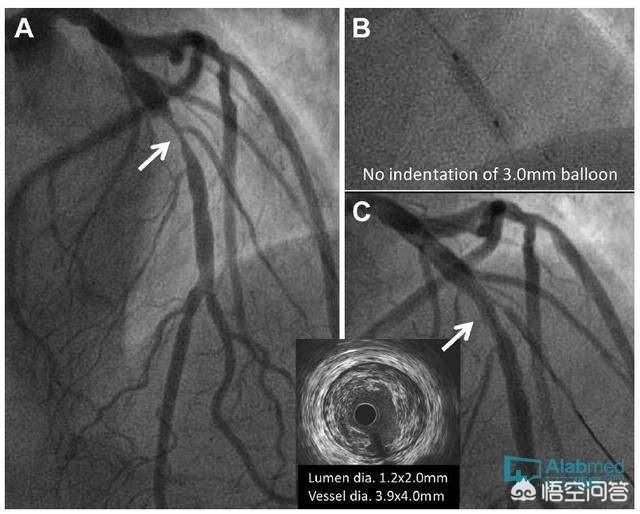

还Certains angors ne sont pas dus à une sténose de l'artère coronaire.Par exemple, le spasme de l'artère coronaire, la microangiopathie coronaire, la cardiomyopathie obstructive hypertrophique, la sténose aortique ou l'insuffisance de fermeture, et même une anémie et une tachycardie sévères peuvent provoquer une ischémie myocardique et des épisodes angineux, qui peuvent survenir chez des patients souffrant d'angine de poitrine, qui n'ont pas nécessairement de sténose de l'artère coronaire. Par conséquent, le pontage aorto-coronarien n'est pas une conséquence nécessaire de tous les cas d'angine.